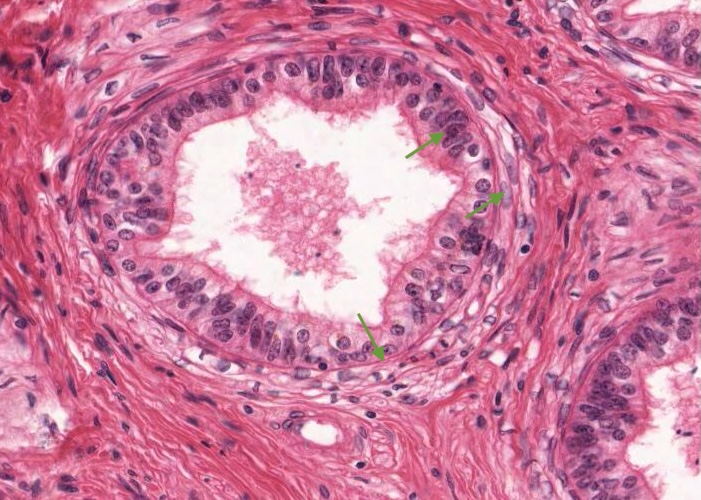

The epithelium of the duct of the epididymis is tall with a uniform thickness. It has two cell types, principal cells (tall columnar cells) each with an elongated nucleus and basal cells (each with a rounded nucleus). You may also see a migrating lymphocyte (halo cell). The principal cells have very long, non-motile, branching cell processes, inappropriately called stereocilia, since they are actually long, modified microvilli. These increase the apical surface area of the cell tremendously for resorption of testicular fluid. Non-motile sperm are stored in this duct and in its extension called the vas deferens. When you examine the histological section you will see dense aggregations of these immature sperm in some cuts through the duct of the epididymis.

The lamina propria around the duct of the epididymis has a small amount of smooth muscle, fibroblasts and capillaries. The circular arrangement of these cells is evident.

As the duct proceeds down towards the tail of the epididymis, the amount of smooth muscle in its wall increases. The circular layer remains but added are an inner layer and outer longitudinal layer, to finally develop a huge, well-organized muscularis layer where it becomes the ductus (vas) deferens.

Notice where the wall of the ductus epididymis has been cut more obliquely, the epithelium and muscularis appear thicker than they appear when cut more transversely.